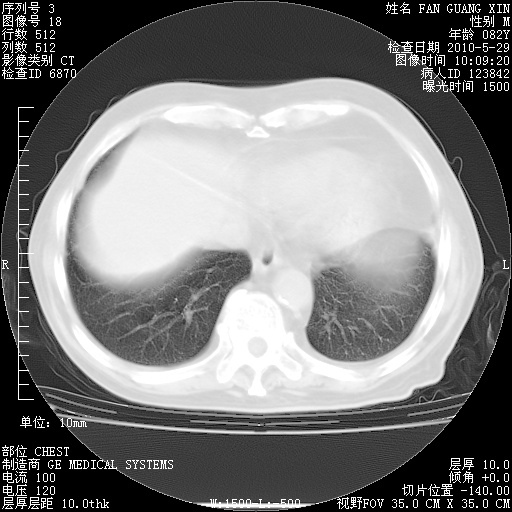

再治疗10天后的肺部CT